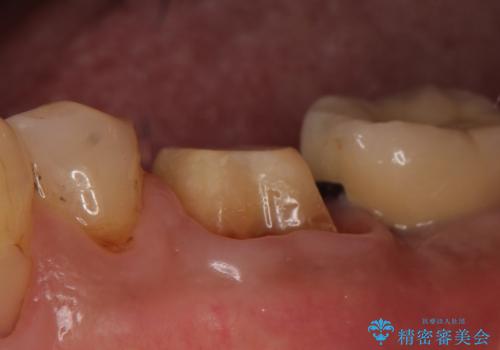

- 左下の奥歯で咬むと痛むので診て欲しいといらっしゃった方の症例です。

検査の結果、左下6番目の歯は神経が死んでおり根尖に病変が出来ていたため、根管治療を行いました。